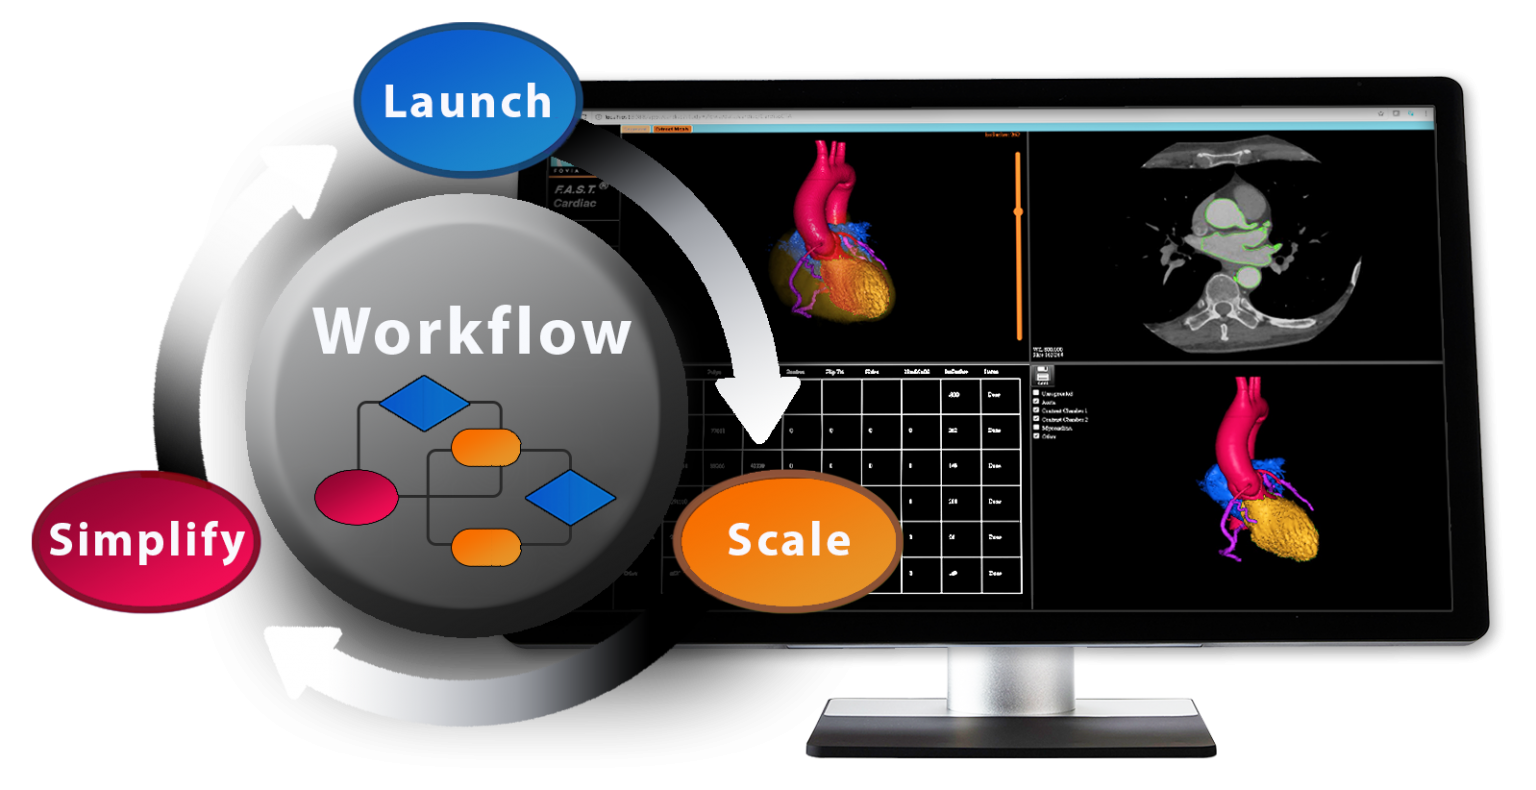

F.A.S.T. Workflows ~ Simplify Development

Representative F.A.S.T. Workflows

Representative F.A.S.T. Workflows